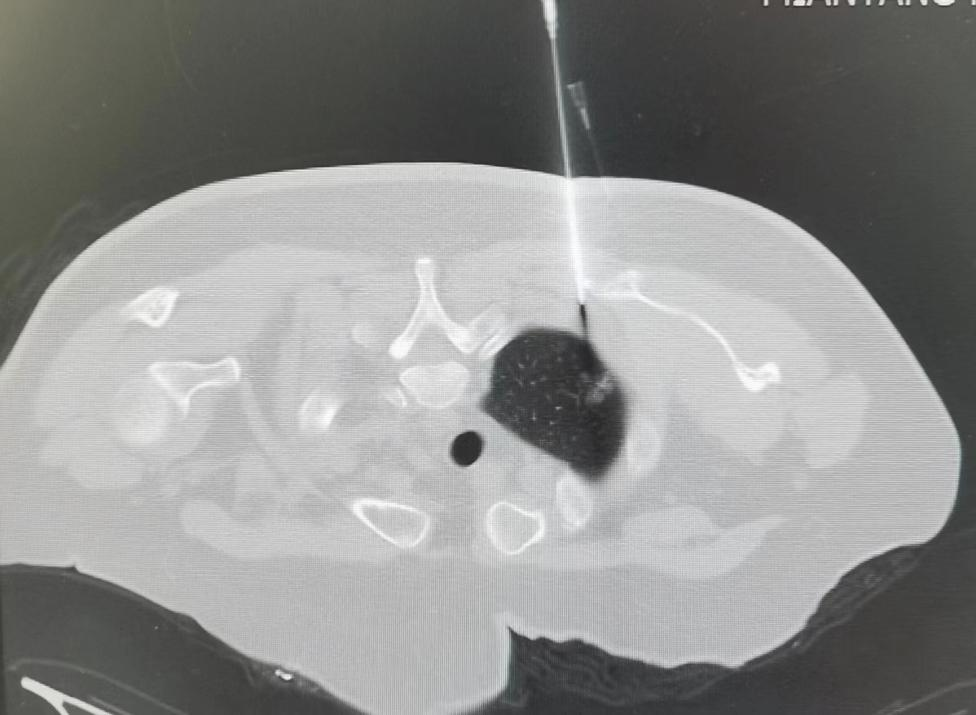

入住肿瘤科后,医护共同对阿姨进行了详细的心理状态评估及检查,在治疗心理疾病的同时,详细对比近几年曹阿姨CT检查变化,考虑右肺上叶尖段磨玻璃结节恶性程度较大,为进一步明确诊断,刘小军医生为其进行了CT引导下经皮右肺上叶尖段磨玻璃结节穿刺活检术,术后病理诊断:原位腺癌。

自2016年以来,肿瘤科已经成功为多例病灶小于1cm肺结节患者通过穿刺活检明确了诊断,为肺癌患者的早诊早治带来了福音。